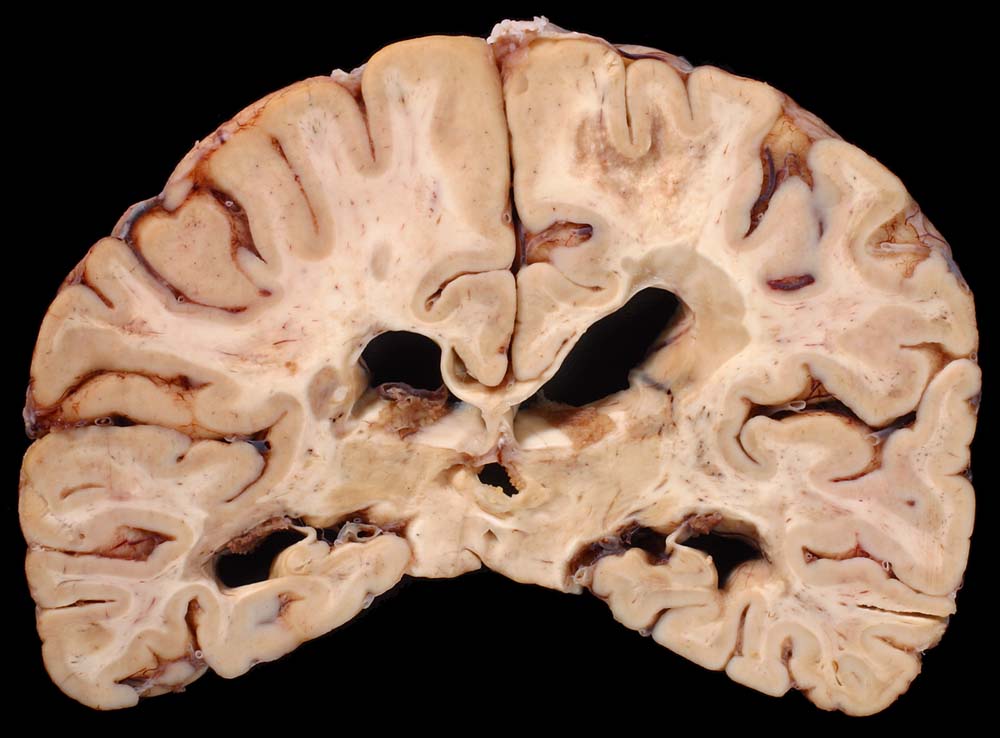

An Frontalschnitten durch das Gehirn fallen makroskopisch Entmarkungsherde vor allem im unmittelbar periventrikulären Marklager auf (um die Vorderhörner, die Cella media und um die Hinterhörner). Nicht selten finden sie sich auch um den Aquädukt und am Boden des 4. Ventrikels. Die Farbe der Herde hängt vom Alter des Prozesses ab (eher rosa bei frischen, eher grau bei alten Herden), die Konsistenz ist weich bei frischen, zunehmend derb bei alten Herden durch Gliafaservermehrung. Histologisch zeigen frische Entmarkungsherde in den ersten Tagen eine Oligodendrogliavermehrung. Ihr folgt mit beginnendem Markabbau eine Mikrogliareaktion. Mikrogliazellen, Monozyten und Makrophagen phagozytieren die Markscheidenzerfallsprodukte (> 10160) (> 10159), die teilweise lichtmikroskopisch im Zytoplasma erkennbar sind (> 10161). Lymphozyten und Plasmazellen sind vor allem perivenös an den Herdrändern lokalisiert. Zusätzlich proliferieren faserbildende Astrozyten (> 10162). In älteren Herden (vorliegendes Präparat) fehlen die Markscheiden praktisch vollständig. Axone bleiben erhalten und es besteht eine dichte Fasergliose. Diese ausgebrannten Herde überwiegen beim chronisch Erkrankten. Auch bei ihm können allenfalls noch frischere Stadien gefunden werden.

Makroskopie

Befund

Pathologischer Befund

Normalbefund